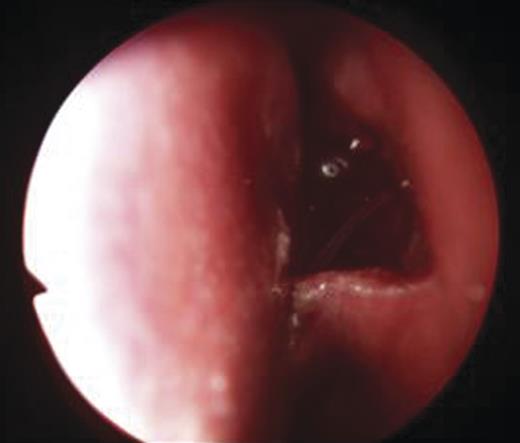

- An endoscopic left anterior ethmoidectomy was performed (Fig. 9) with marsupialisation of the mucocele (Fig. 9) and trimming of the DCR stent (Fig. 10)

Figure 9:Transnasal endoscopic left anterior ethmoidectomy and marsupialization of mucocele.

Figure 10:Post-operative view with trimmed DCR stent in situ in the left nasal cavity.

Post-operatively, she was discharged the next day and advised to administer chloramphenicol eyedrops as well as betnesol nasal drops for a week. The DCR stent remained in situ for 3 months and was removed in the clinic. There was clinical resolution of the medial canthal swelling and epiphora.